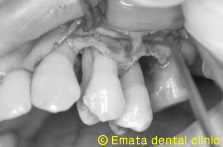

術中です。 |

CT導入してから歯周病の進行度が確実に分かり、抜歯の適応か、再生療法が可能か、従来の「開けたとこ勝負」的な歯周外科も事前に線密なプラニングが可能になり、まさに画像診断の革命が始まったという実感です。